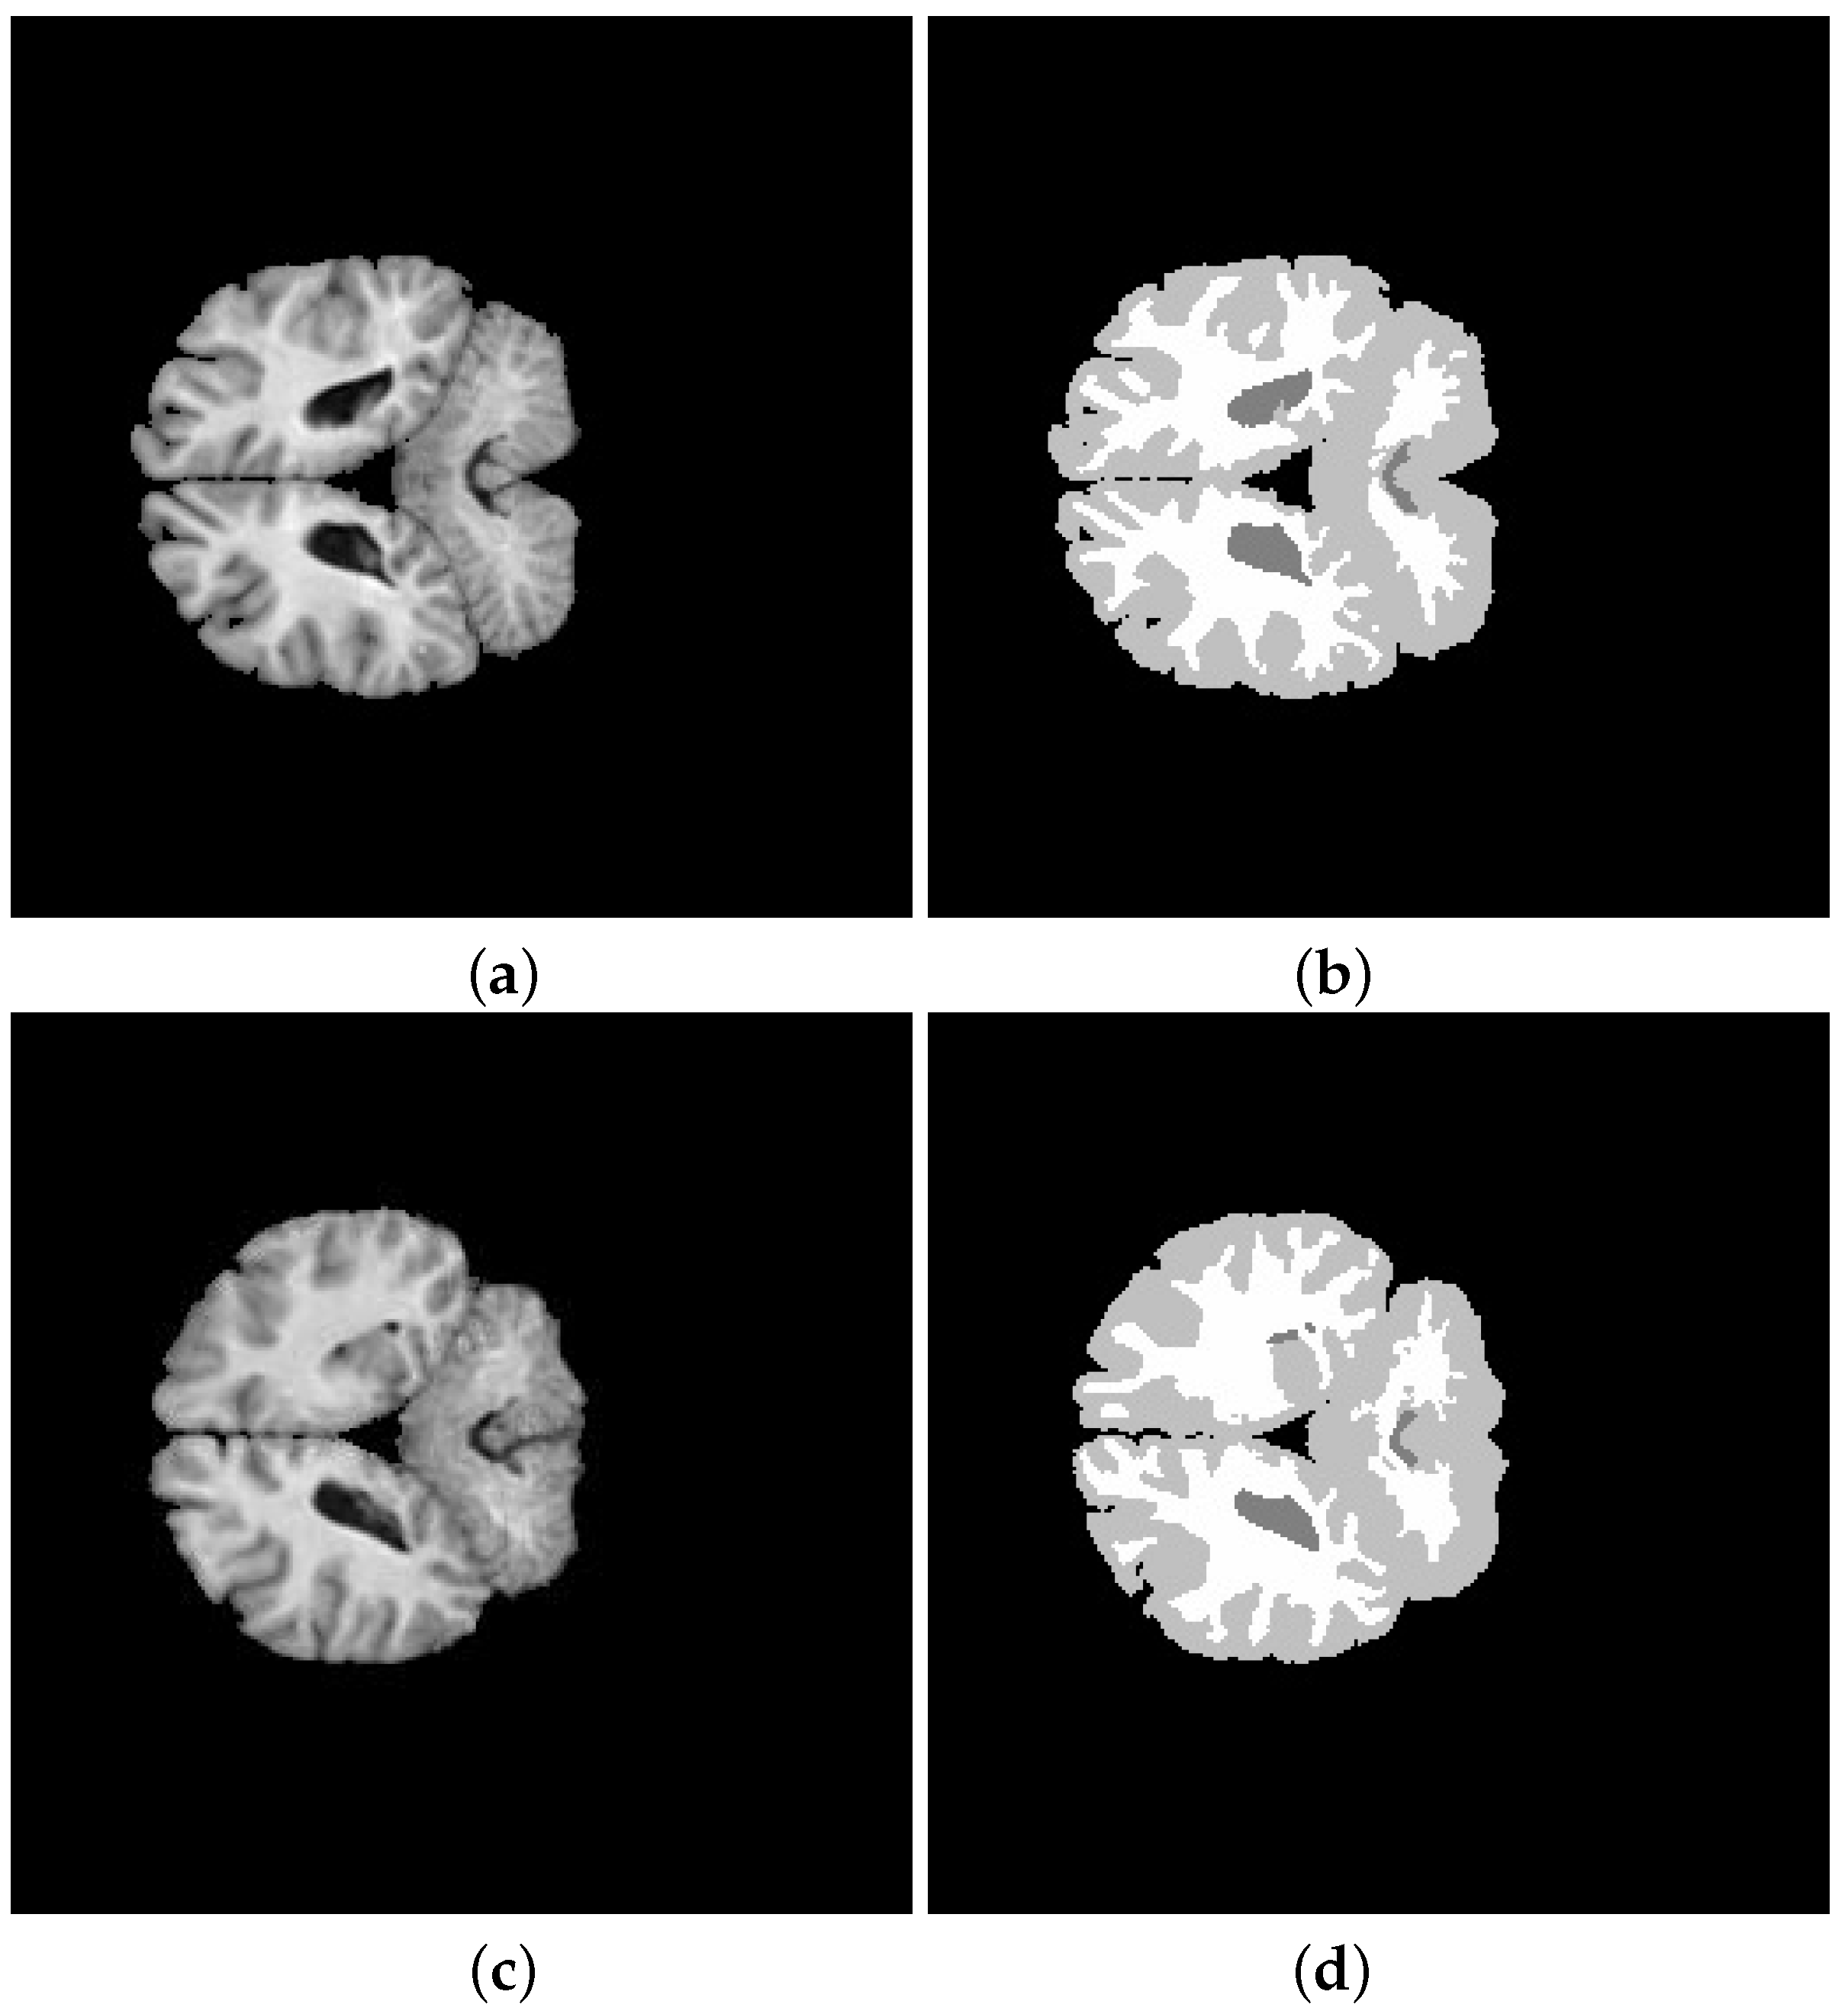

| Subject | Method | JS | DSC | Sensitivity | Specificity | Accuracy |

|---|---|---|---|---|---|---|

| K-means | % | |||||

| 202-3 | ||||||

| 0.8938 | 0.9486 | |||||

| K-means | ||||||

| 205-3 | ||||||